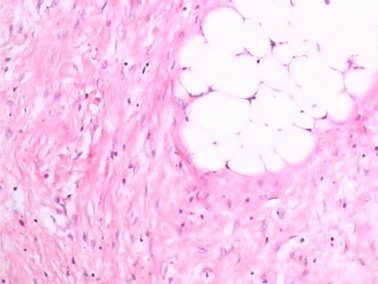

肿瘤细胞由梭形细胞构成,排列成束状、席纹状或片状,弥漫浸润至周围脂肪,如下图1。

图1 (HE×100)